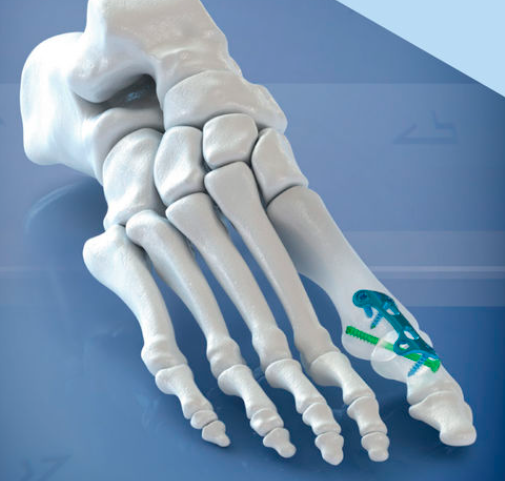

♦ 뼈 절골술(뼈 자르기 및 배열 교정): 변형된 뼈를 잘라내거나 교정하여 엄지발가락을 바른 위치로 재정렬합니다.

♦ 연부 조직 교정술: 엄지발가락 주위의 인대, 힘줄 등 연부 조직을 조절해 균형을 맞춥니다.

(보통 뼈 절골술시 같이 시행함)

♦ 관절 고정 및 인공 관절술: 퇴행성 관절염이 동반된 경우 관절을 고정하거나 인공 관절로 치환할 수 있습니다.